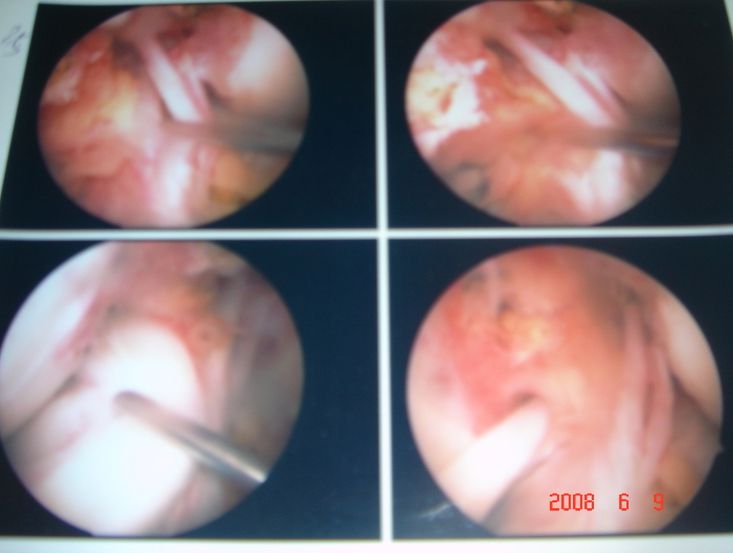

관절내시경 사진

관리자

| 2008.10.22

| 1865